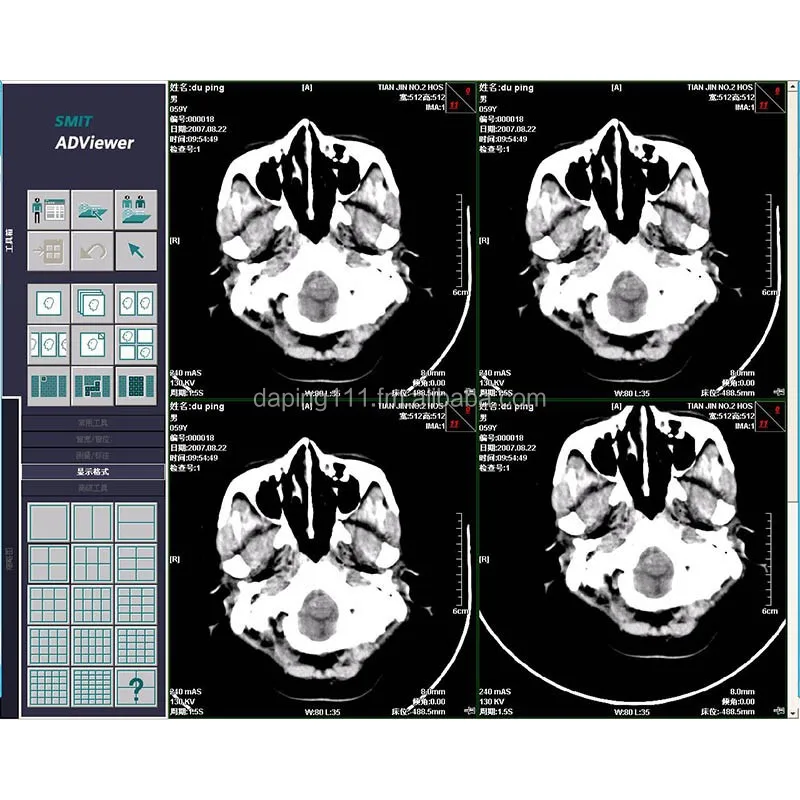

Software Of CT Workstation

- Category:

- Supplier: MarchCreative,Tech.,Co.,Ltd.,[Liaoning,China]MarchCreative

RUB 46,238.94

In Stock